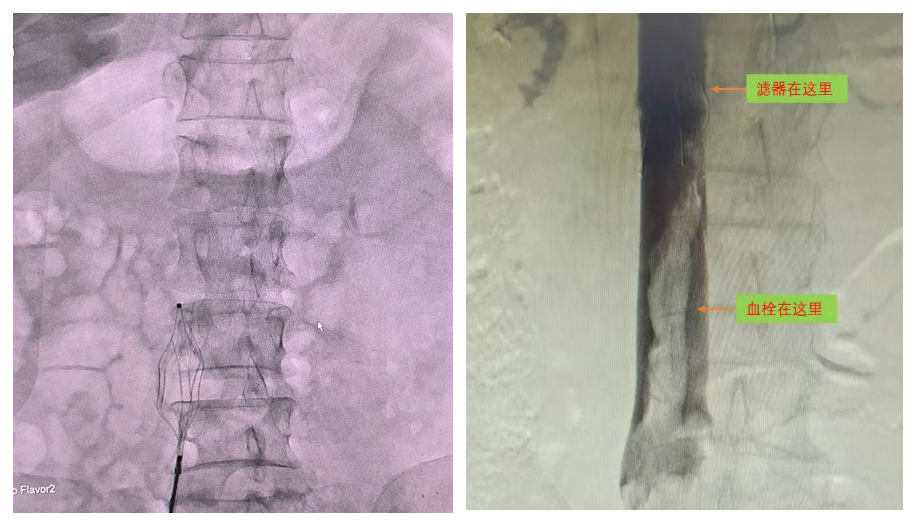

滤器在体内发挥作用

腔静脉滤器:守护生命的坚固盾牌

下肢深静脉血栓最严重的风险是肺栓塞,极容易引发猝死。通过微创介入植入滤器“网住”脱落血栓,可对下肢深静脉的游离血栓进行有力阻拦、捕捉,既能阻挡血栓进入肺动脉,又不影响静脉回流,从而预防致死性肺栓塞发生,为患者撑起安全“保护伞”。